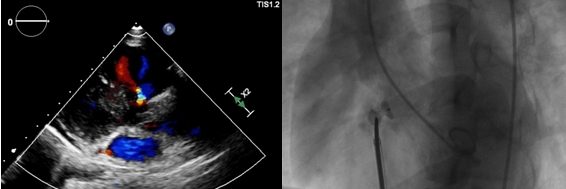

此次手术由陈弹主任医师主刀,董瑞庆博士辅助,杨俊华主任医师全程超声配合。成功置入了6mm大小的“迷你版”封堵器,术中超声心动图及DSA造影确认封堵完全,心电监护亦未见房室传导阻滞,手术顺利完成。

七、2021.05.14我院第一台在心腔内超声指导下的左心耳封堵术:

此次手术为我院首台心腔内彩超(ICE)指导下的左心耳封堵术,也是我市少有的基于ICE建模,局麻下完成的封堵术。术者为我院心内科陈弹主任医师。其意义不仅在于为房颤患者提供新的预防卒中的策略,还标志着我院心血管内科团队在心脏介入诊疗领域迈上了新台阶。